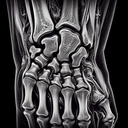

МРТ променезап'ясткового суглобу

МРТ променезап'ясткового суглоба – це неінвазивний метод дослідження, який дозволяє отримати детальну інформацію про м'які тканини, кістки та зв'язки в зоні зап'ястка. Він особливо корисний для виявлення травм, запальних процесів, дегенеративних змін та новоутворень. Переваги МРТ: 1...